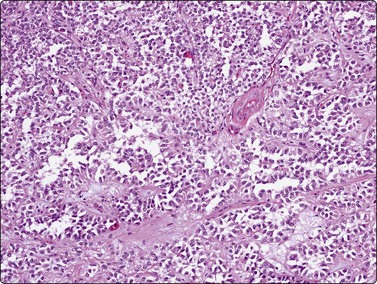

Intraductal papillary mucinous and mucinous cystic neoplasms (Figs 11.12-11.14)

image image image

Fig. 11.12 Intraductal papillary-mucinous neoplasm (IPMN)

(A) Large multilayered papillary structures; note the smooth borders (H&E, IP); (B) Small papillary clusters of cuboidal epithelial cells with mucin vacuoles; the pale mucin in the background is not easily seen (Pap, HP); (C) Cell block showing strips and papillary formations of atypical columnar epithelium (H&E, IP).

image

Fig. 11.13 Intraductal papillary-mucinous neoplasm (IPMN)

Tissue section corresponding to Figure 11.12 (H&E, IP).

Fig. 11.14 Mucinous cystic neoplasm (MCN)

(A, B) Clusters and sheets of relatively monotonous malignant glandular cells showing intracytoplasmic mucin vacuoles (A, MGG, HP; B, H&E, HP); (C) PAS diastase stain on cell block material highlights the intra- and extracellular mucin (PAS/D, IP).

Criteria for diagnosis

Abundant background mucin,

Cohesive sheets and papillary aggregates,

Cuboidal to columnar, mucin-filled cells,

Spectrum of nuclear changes

Distinction between IPMN and MCN on cytologic grounds is problematic and requires correlation with clinical, imaging and endoscopic findings as the clinico-radiologic characteristics are very different.

Intraductal papillary-mucinous neoplasms (IPMN) were first described as a distinct entity in the 1980s.83 They are now well characterized as tumors of better prognosis as they have a long intraductal course but eventually will invade into periductal pancreatic parenchyma, and then go on to nodal and distant metastases.84 Both sexes can be affected, but elderly males predominate. IPMN usually involves the main duct in the head of the pancreas but can arise in side branches. As the name implies, the lining epithelium is both papillary and mucinous. The duct system is filled with viscous mucus, leading to a very characteristic endoscopic appearance, where the ampulla of Vater is often seen to be patulous, and draining mucin. The cytology is distinctive (but not entirely specific), showing abundant background mucin, in which sheets and papillary aggregates of cuboidal to columnar, mucin-filled cells are seen (Figs 11.12 and 11.13). Several reports attest to the ability of cytology to diagnose these good-prognosis tumors preoperatively, in conjunction with radiologic and endoscopic features.84-86 In a series of 19 patients, a sensitivity of 82% and specificity of 100% was reported.87

The classic mucinous cystic neoplasm (MCN) is an indolent tumor of middle-aged females, the majority occurring in the tail of the pancreas. These tumors show a spectrum of grade and behavior including benign cystadenomas, borderline forms, and malignant cystadenocarcinomas. The latter obviously has a poorer prognosis if invasion has occurred. Radiologic studies identify a usually discrete and obviously cystic mass in the pancreatic tail. As there is no communication with the pancreatic ductal system, endoscopy does not demonstrate mucinous discharge from a patulous ampulla. As with IPMN, cytology shows a background of copious extracellular mucin, in which cohesive monolayered sheets of mucinous columnar cells are found (Fig. 11.14). These demonstrate regular to irregular honeycombing, with a spectrum of nuclear changes depending on the stage of tumor progression. Epithelial cell cytoplasm is distended with mucin vacuoles.88-91